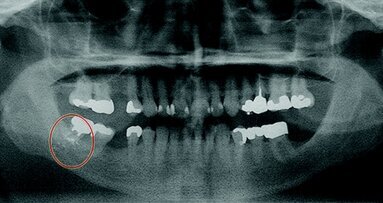

Fig. 1 - Dettaglio paziente del gruppo 3: Trattamento AIRFLOW® a due mani con aspirazione ad alto flusso e Optragate: un sistema a ciclone pre riempito con acqua filtrata (PRELECT, Medentex GmbH, Bielefeld, Germania) è stato posizionato a circa 20 cm a sinistra della bocca del paziente per raccogliere gli aerosol.

Materiali e metodi I trattamenti AIRFLOW sono stati eseguiti nelle sale di profilassi della società EMS (Nyon, Svizzera) da una dentista (Dr. Neha Dixit, EMS). La procedura di misurazione e le condizioni generali per l’esecuzione della profilassi erano state precedentemente progettate dagli autori. In totale sono stati trattati 20 pazienti adulti di età compresa tra i 30 e i 45 anni. L’indice della placca Quigley- Hein modificato secondo Turesky [Turesky et al., 1970] era di 0,80. Le sessioni di profilassi si sono svolte in quattro giorni consecutivi con cinque pazienti ciascuna. Tra un trattamento e l’altro, le stanze sono state accuratamente ventilate per rimuovere gli aerosol rimasti e ripristinare una situazione neutrale per la sessione successiva. L’aerosol è stato misurato per dieci minuti esatti ad ogni trattamento AIRFLOW. Per raccogliere gli aerosol è stato utilizzato un sistema a ciclone (PRELECT, Medentex GmbH, Bielefeld, Germania) precaricato con acqua filtrata e collocato a 20 cm dalla bocca del paziente (Fig. 1).

Fig. 1 - Paziente del gruppo 3: Trattamento AIRFLOW® a due mani con aspirazione ad alto flusso e Optragate: un sistema a ciclone pre riempito con acqua filtrata (PRELECT, Medentex GmbH, Bielefeld, Germania) è stato posizionato a circa 20 cm a sinistra della bocca del paziente per raccogliere gli aerosol.